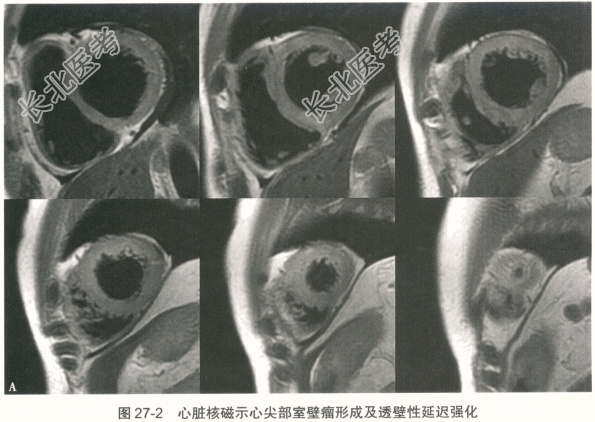

患者男性,41岁,2016年2月20日晚间无明显诱因出现发热,体温最高38.0℃,伴轻微胸闷、憋气、头晕、头痛、恶心,偶有呕吐及四肢酸痛,无胸痛及肩背部放射痛,自行服用对乙酰氨基酚1片后症状不缓解。21日晨起体温38.5℃,伴全身乏力,至当地医院行胸片检查未见明显异常,行血常规检查提示白细胞、中性粒细胞偏高(具体数值不详),考虑炎性病变,回当地诊所继续输液治疗(药名及剂量不详),效果欠佳。22日上午患者出现胸闷、憋气、四肢无力,伴恶心,无呕吐,输液期间症状反复发作,逐渐加重。23日2:00胸闷、憋气明显,突发意识丧失,急呼120送至保定市第一中心医院,检查结果示:CK-MB39.6ng/ml↑,肌红蛋白431.0ng/ml↑,肌钙蛋白18.4ng/ml↑,BNP536.00pg/ml↑,D-二聚体0.7μg/ml↑,ALT615.00U/L↑,AST781.00U/L↑,肌酐204.9μmol/L↑,当地医院诊断"重型心肌炎",给予抗炎、抗病毒治疗,静脉泵入异丙肾上腺素、多巴胺及甲泼尼龙,体温逐渐回落至正常,但胸闷、憋气、乏力等症状无缓解。当晚17:00左右送至我院急诊科,转运过程中胸闷、憋气症状进行性加重。心电图示:三度房室传导阻滞。心脏超声:左室整体功能减退,二、三尖瓣轻度反流,少量心包积液,未见节段性室壁运动障碍。我院给予异丙肾上腺素、甲泼尼龙冲击、盐酸多巴胺等治疗,给予急诊临时起搏器。随后收入我科,心电图提示加速性室性自主心律。吸烟史10余年,约20支/天,无饮酒史,家族无遗传病史。 入科后因临时起搏导管感知不良,更换临时起搏器期间患者突然出现意识丧失,伴抽搐,持续约2分钟后患者意识逐渐恢复,但躁动明显,伴呼吸困难,氧饱和度维持在85%左右,行气管插管术,吸出大量粉红色泡沫样痰,给予托拉塞米40mg静脉推注,呼吸机持续辅助呼吸,氧饱和度逐渐回升至100%。入科后查体:血压71/49mmHg,心率55次/分,双肺大量湿啰音,心音低钝,未闻及明显杂音。检查:CK-MB、肌红蛋白、肌钙蛋白、D-二聚体、ALT、AST、γ-GGT、肌酐均升高,BNP>35000pg/ml,血常规示:白细胞计数和中性粒细胞升高。2月23日肺部CT提示双侧肺水肿,双侧胸腔积液。经应用激素及其他辅助药物治疗后,患者病情逐渐稳定,临床症状及化验检查.心电图、胸部CT均明显改善。 患者3月7日复查超声心动图提示心尖部室壁瘤形成,不除外心肌梗死所致(图27-1)。因而进一步行冠脉CT及心脏磁共振。冠脉CT未见明显冠状动脉狭窄。心脏磁共振:①左室心尖节段性延迟强化并反向运动;②左侧-侧壁心肌弥漫水肿并延迟强化,明确有室壁瘤形成(图27-2)。3月7日EBV-DNA定量检测阳性,C-反应蛋白6.28mg/dl。